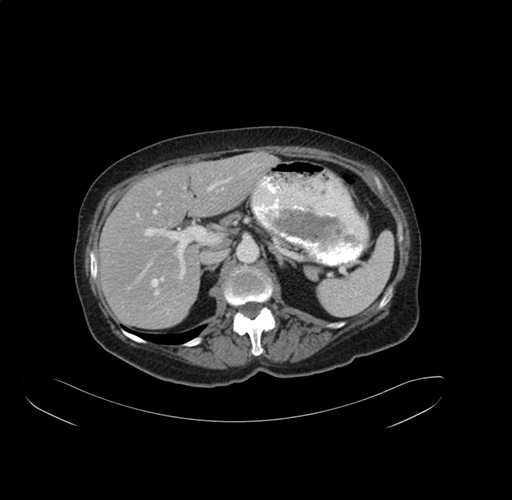

Pre-Chemo: Axial Venous

Axial Venous